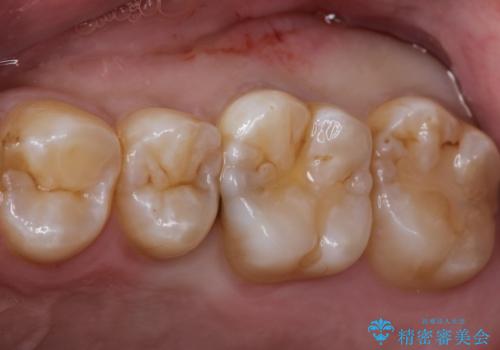

臼歯 咬合の再構成

担当医 大元洋佑